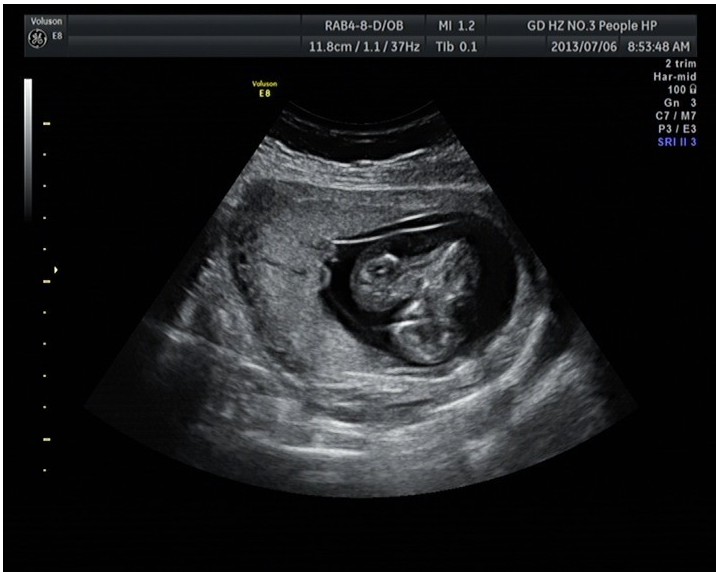

随着环境污染日益严重,随着各种地沟油的诞生,随着各样镉大米的泛滥……我们的健康越来越受到威胁,很多疾病也随之接踵而至,胎儿先天性疾病也越来越多见。7月6日,我院超声科王瑶医生在做胎儿产前NT筛查中发现一例孕约11周+的联体双胎。超声所见:增大的子宫内可见联体双胎儿回声,可见两个胎头不能分离,胸部及腹部融合,可见一个增大的心脏。

联体婴儿B超图像